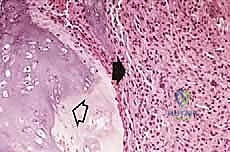

مبادئ الاستئصال الجراحي: الهوامش الجراحية (Surgical Margins)

الهدف الأول في جراحة الساركوما ليس فقط إزالة الكتلة المرئية، بل استئصالها مع طبقة من الأنسجة السليمة المحيطة بها لضمان عدم ترك أي خلايا مجهرية. تُصنف الهوامش الجراحية إلى:

- الاستئصال داخل الورم (Intralesional): يتم قطع الورم من الداخل. غير مقبول في الساركوما الخبيثة.

- الاستئصال الهامشي (Marginal): الاستئصال عبر الكبسولة الكاذبة للورم. يحمل خطر عودة الورم (Recurrence).

- الاستئصال الواسع (Wide Resection): وهو المعيار الذهبي. يتم استئصال الورم مع طبقة من الأنسجة السليمة المحيطة به (العضلات، العظام). هذا ما يبرع فيه الدكتور هطيف لضمان الشفاء التام.

- الاستئصال الجذري (Radical Resection): استئصال كامل الحيز العضلي أو العظمي الذي يحتوي على الورم.

يتم تقييم مدى استجابة الورم للعلاج الكيميائي (Tumor Necrosis Rate) بعد الاستئصال، وهو مؤشر قوي لفرص الشفاء التام.